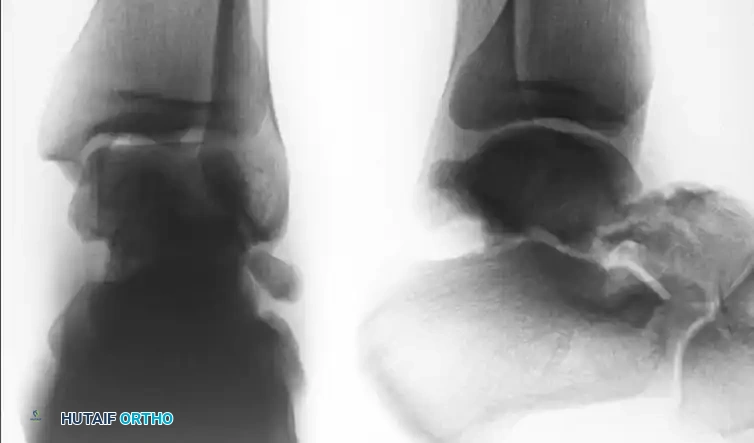

Standard radiographic evaluation includes anteroposterior (AP), lateral, and mortise views of the ankle, alongside standard foot radiographs. However, plain radiography often underestimates the degree of comminution and displacement.

The Canale View

To accurately assess varus or valgus alignment of the talar neck, the Canale view is mandatory. The foot is placed in maximum equinus and pronated 15 degrees, with the x-ray beam directed 75 degrees cephalad from the horizontal. This provides an optimal en face view of the talar neck.